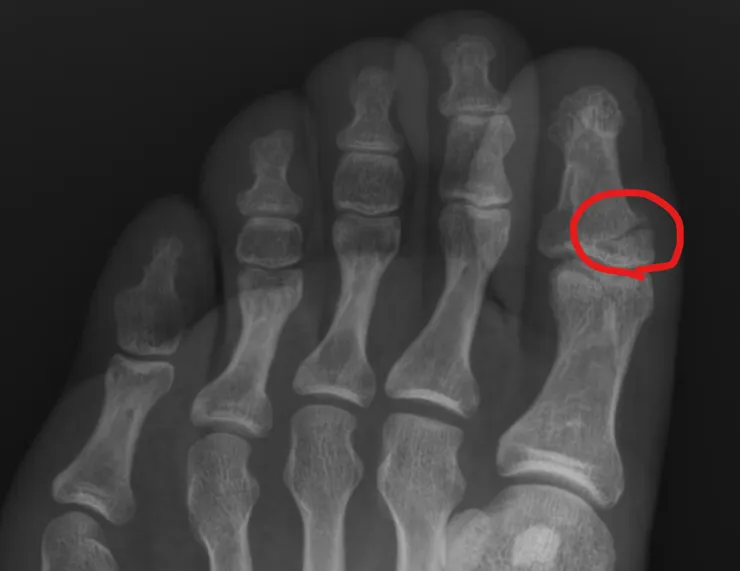

前腳拇指骨折,

或許有人會以為是小骨折吧!?

但其實我覺得算很嚴重,

來附個傷照。